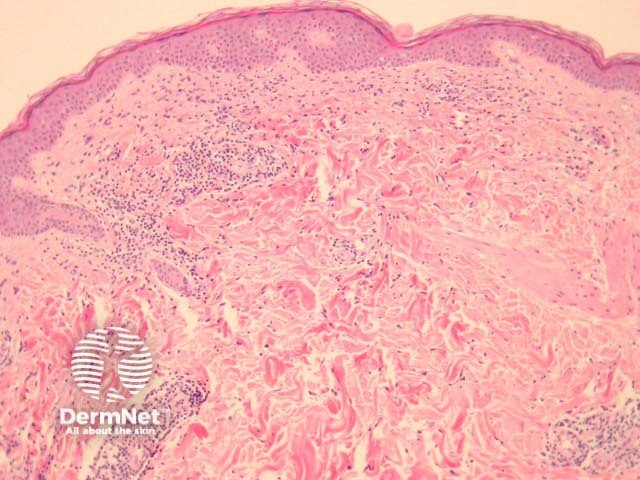

Biopsy of erythema migrans reveals a sparse superficial and deep infiltrate under an uninvolved epidermis (figure 1). Sometimes there is epidermal and/or dermal necrosis. High power examination reveals the infiltrate is mainly lymphocytic (figure 2). There are often sparse eosinophils, admixed plasma cells and mast cells.

Figure 2